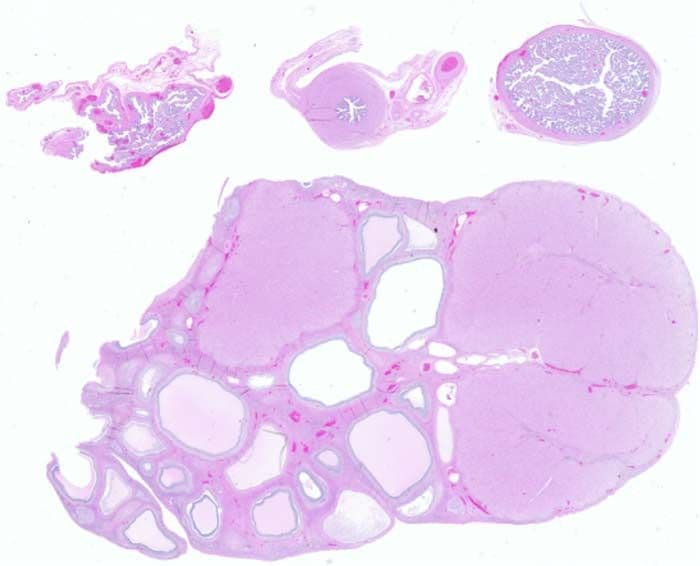

For tissue section imaging, a tissue or organ is excised, embedded to preserve it, cut into sections, stained, and then mounted onto slides for imaging. If you are tracking a therapeutic agent or optical probe, you would introduce those before excising the tissue. Proteins or other targets of interest—such as mRNA, RNA, and DNA—can then either be directly detected by the labeled agent or with the aid of dye-labeled antibodies, optical probes, or visible stains, such as H&E stain or Alcian blue. Finally, image the tissues using an imager, such as the Odyssey M Imager.

Scientists use histological staining to create contrast in tissue features. Histological stains, such as H&E stain, Alcian blue, and Evans blue, allow for the study of tissue structure and help identify the presence or absence of diseased tissue at the macroscopic level.